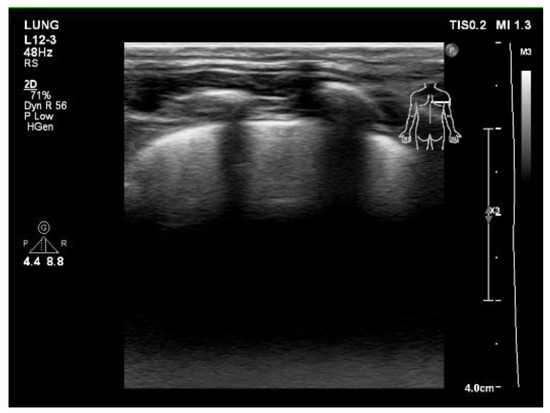

A series of examinations was performed to establish the final diagnosis. Her blood gas pH value was within the normal range, without carbon dioxide retention or metabolic acidosis. A chest x-ray showed diffusely increased density of both lungs (Figure 1A). Lung echo suggested pulmonary edema (Figure 2), and furosemide was administered. Chest

Figure 2. Lung echo showed multiple B lines (comet-tail artifacts), suggesting pulmonary edema.